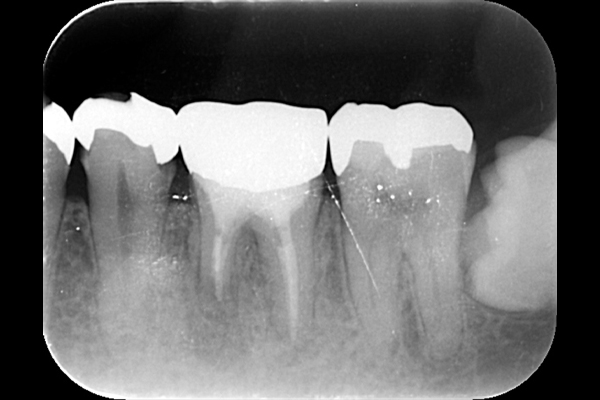

それは歯の先に枝分かれが多く存在し、そこにばい菌が入り込んで難治性となっているからです。ではその場合どうするのか?外科治療をします。その枝分かれの部分を切り落とすのです。今回はその前後のレントゲンの写真をお見せします。

| 根の先の黒い影は消失しました。 | 術後6ヶ月のCT画像です。こちらでも、根の先に黒い影は見当たらないです。 |

このように外科的治療で病変部を切除することでしっかりと治癒させることが可能です。根の治療は細菌との戦いです。難しいですが、やりがいがあります。